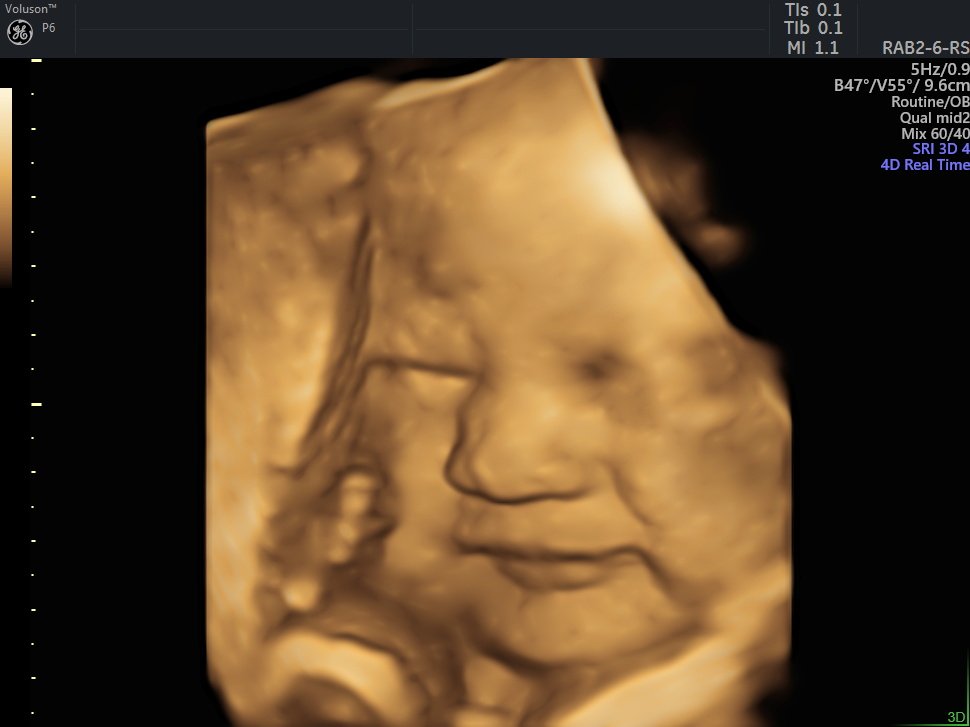

4 D Ultrasonografi

4 Boyutlu (Renkli) Ultrason ve Doppler Ultrasonografi